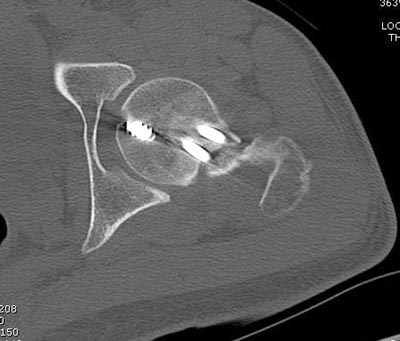

несращения! По истечению 4 месяцев появились признаки варусной

деформации. На СТ срезах несращение шейки и бедра. Риминг, замена на

более толстый гвоздь и вальгусная остеотомия.